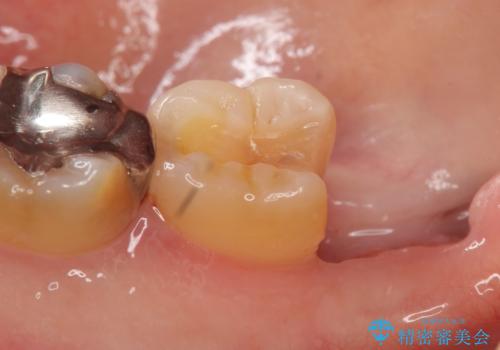

- 右下奥歯がたまにしみるので診て欲しいといらっしゃった方の症例です。

右下7番目の歯の歯茎より深い位置に虫歯があったため、親知らずを抜歯後PGA(ゴールド)インレーによる修復を行いました。